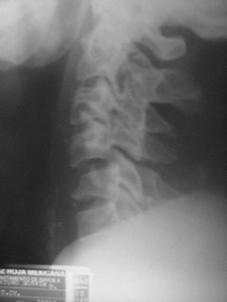

TRAUMA CERVICALA

Incidenta oblica Incidenta laterala Incidenta antero-posterioara

Aspect normal Aspect normal Aspect normal

Fractura spanzuratului Fractura anterioara C4 Fractura C5 in lacrima in flexie

"in lacrima"

Fractura C5 "in lacrima" in extensie Luxatie fatetara

unilaterala Luxatie

fatetara bilaterala

C5 - C6 C5 - C6

Incidenta laterala Fractura Clay-Shoveler Luxatie atlanto-occipitala si